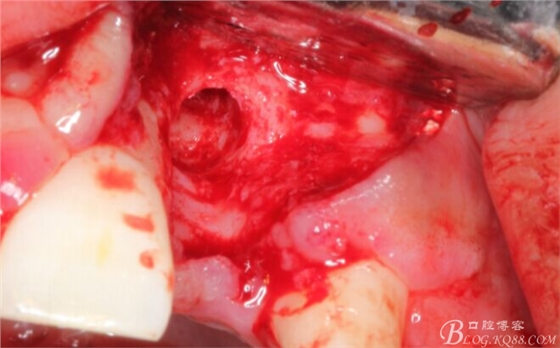

再次翻瓣。

先行粘骨膜減張,取自體血液。

根方用取骨鉆取自體骨。

旋入一長兩短3顆鈦釘。

將自體骨與BIO-OOS骨粉混合植到術(shù)區(qū),蓋生物膜。